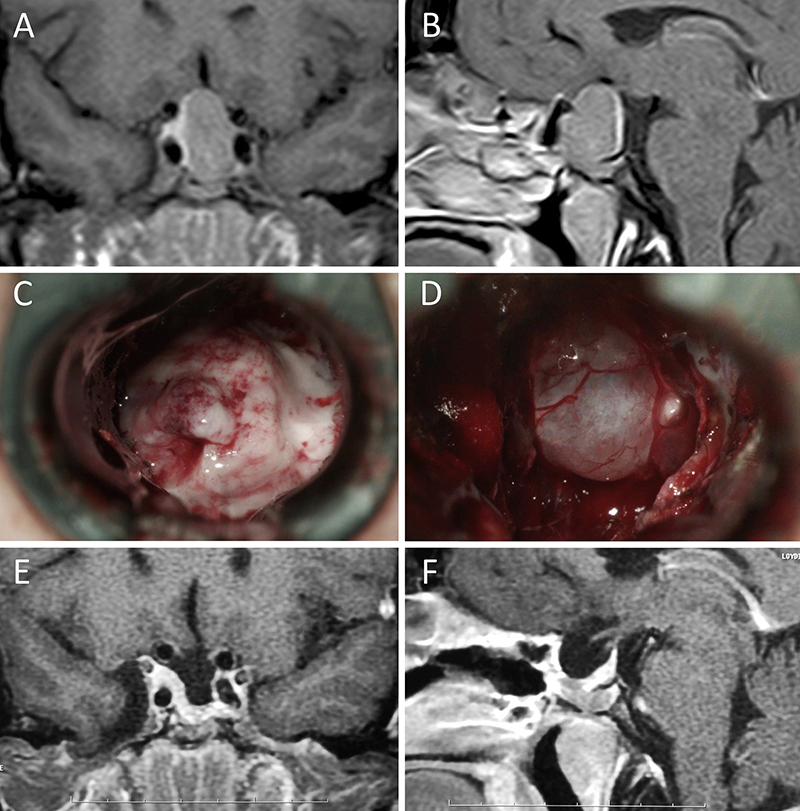

Figura 11: Microadenoma en una mujer de 36 años con Enfermedad de Cushing. Con remisión bioquímica tras la cirugía. A-B: RM preoperatoria; C-D: intraoperatorio; E-F: RM postoperatoria.

Figura 12: Microadenoma en una mujer de 26 años con Enfermedad de Cushing. Con remisión bioquímica tras la cirugía. A-B: RM preoperatoria; C-D: intraoperatorio; E-F: RM postoperatoria.

Figura 13: Macroadenoma en una mujer de 42 años con Enfermedad de Cushing. Con remisión bioquímica tras la cirugía. A-B: RM preoperatoria; C-D: intraoperatorio; E-F: RM postoperatoria.